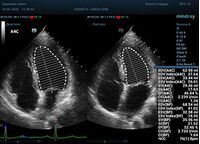

С появлением В режима реализовалась возможность визуализации всех сегментов миокарда из парастернальных и апикальных сечений. Метод Teicholtz в широкой практике сменился методом дисков. Метод дисков, или метод Simpson, позволяет разбить левый желудочек на 20 дисков, с расчетом объема каждого из них. Используя 2 перпендикулярных сечения, апикальные двух и четырех камерное, мы приближаемся к значению реального объема левого желудочка. Исследователь обводит интерфейс эндокард – кровь в фазу диастолы и фазу систолы. Линия простирается от кольца митрального клапана и до кольца митрального клапана, четко разграничивая объем желудочка от предсердия. Для достоверного изменения необходимо использовать ЭКГ канал.

Обводить вручную эти линии занимало много времени, однако результат того стоил. Следующим шагом стало появление Spline технологии, позволяющее расставлять точки и автоматически их соединять. Такой способ планиметрии контура эндокарда значительно сократил время измерения.

Что могут предложить современные приборы? Приборы нашего времени являются мощными вычислительными машинами, способными обрабатывать полученную информацию даже без помощи человека. Система автоматического вычисления фракции выброса – AUTO EF на

приборах серии Resona компании Mindray сделает все за вас. За пару секунд прибор сам отыщет нужную фазу сердечного цикла и произведёт измерение и расчеты, а также покажет график изменения объема в сердечном цикле. От Вас требуется только получить качественное 4С и 2С сечение. Впрочем, прибор всегда оставляет возможность коррекции, если доктор имеет свое мнение на расположение точек планиметрии или момента измерения по ЭКГ каналу.